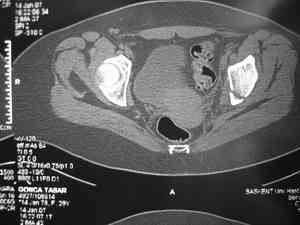

Это наблюдение 5-летней давности тогда кровопотеря составила 2,5 литра. В настоящий момент мы теряем не более 0,7-1,5 литров при одностороннем повреждении и около 2,5-3 литров тогда, когда речь идет о двусторонних повреждениях. Клинический пример.

прилагаю пример с такой же давностью травмы, репонировали аппаратом